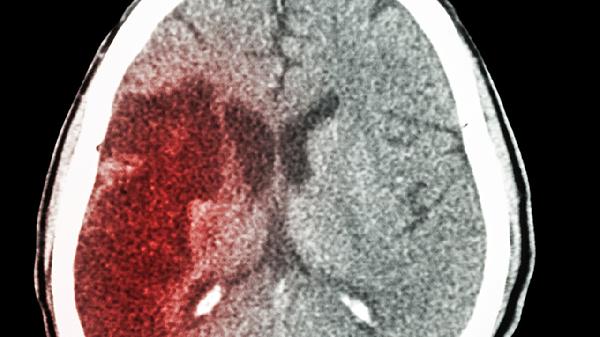

脑梗前兆症状主要包括突发性头晕、肢体麻木无力、言语不清、视物模糊、行走不稳等。脑梗可通过控制危险因素、药物治疗、手术治疗、康复训练、定期随访等方式治疗。脑梗通常由高血压、动脉粥样硬化、心脏病、糖尿病、吸烟等因素引起。